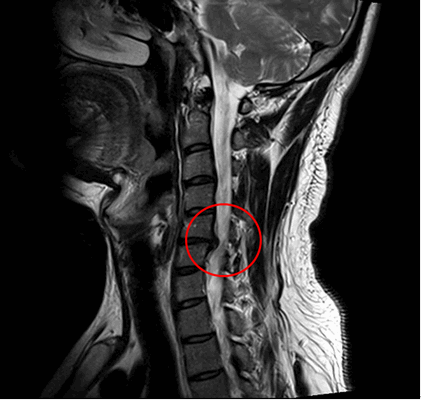

Шейный (цервикальный) отдел - самая подвижная часть позвоночной системы, имеющая изначально узкий позвоночный канал и богатую нервно-сосудистую сеть. Его позвонки отличаются мелкими размерами и специфичным строением, при этом мышечный каркас, который осуществляет поддержку и работоспособность шейных элементов позвоночника, анатомически недостаточно сильный и выносливый. Все это объясняет широкую распространенность возникновения именно в этой хребтовой зоне различного рода дегенераций и травматических повреждений, характеризующихся яркой неврологической симптоматикой.

Однако большую тревогу вызывает тот факт, что шейные патологии часто сопровождают очень серьезные последствия, среди которых парез и паралич конечностей (особенно рук). Кроме того, запущенные формы болезней могут провоцировать тяжелую дыхательную недостаточность, стремительное ухудшение зрения и слуха, острое нарушение кровообращения в тканях головного мозга и пр. Поэтому лечение цервикальной зоны позвоночного столба предельно важно начинать как можно раньше, как только человек почувствовал первый дискомфорт в соответствующей области.

В противном случае заболевание примет агрессивный характер, что приведет к сильному сужению спинального канала, защемлению нервных корешков и/или пережиму артерий, возможно, к поражению спинного мозга со всеми вытекающими последствиями. Тяжелые состояния лечатся исключительно хирургическим путем.

Операция при стенозе шейного отдела позвоночника

Под стенозом шейного отдела принято обозначать патологическое сужение просвета позвоночного канала, где располагается одна из главных структур ЦНС - спинной мозг. При данной патологии зачастую необходимо срочно вовлекать нейрохирургию, так как она опасна критическим неврологическим дефицитом и вегетативными расстройствами. Цервикальная стриктура может привести к ишемии головного и спинного мозга, параличу верхних конечностей (могут пострадать и ноги) и даже к парализации всей части тела ниже пораженной области.

Первопричиной стеноза шейного отдела в доминирующем количестве случаев является последней стадии остеохондроз, операция при спинальном сужении рекомендуется как спасение от тяжелой инвалидизации больного. Стоит заметить, что остеохондроз нами указан как обобщающее понятие, включающее широкий спектр заболеваний, которым положил начало именно данный дегенеративно-дистрофический патогенез. В группу патологий, которые развились на почве запущенного остеохондроза, относят межпозвоночные грыжи, краевые разрастания на позвонках, спондилоартроз, окостенения связок и многие другие.

Стеноз шейного отдела вследствие грыжевого выпячивания.

Наибольшее распространение операция получила при стенозах позвоночного канала. Как показывают практические наблюдения, сужение диаметра позвоночного канала диагностируется довольно часто, причем в 75% случаев на уровнях поясничного отдела. На люмбальном уровне l4 l5 такого типа нарушение обнаруживается чаще всего, немного реже его определяют на l3 l4. Таким образом, зона l3 l5 (от 3-го до 5-го позвонка) в целом является тем основным эпицентром, где стеноз преимущественно локализируется. И ламинэктомия по поводу стеноза, соответственно, применяется на указанных уровнях чаще, чем где-либо. Что касается остальных отделов, патологию спинального канала в шейной части позвоночника выявляют примерно в 25% случаев, в грудном отделе недуг развивается крайне редко.